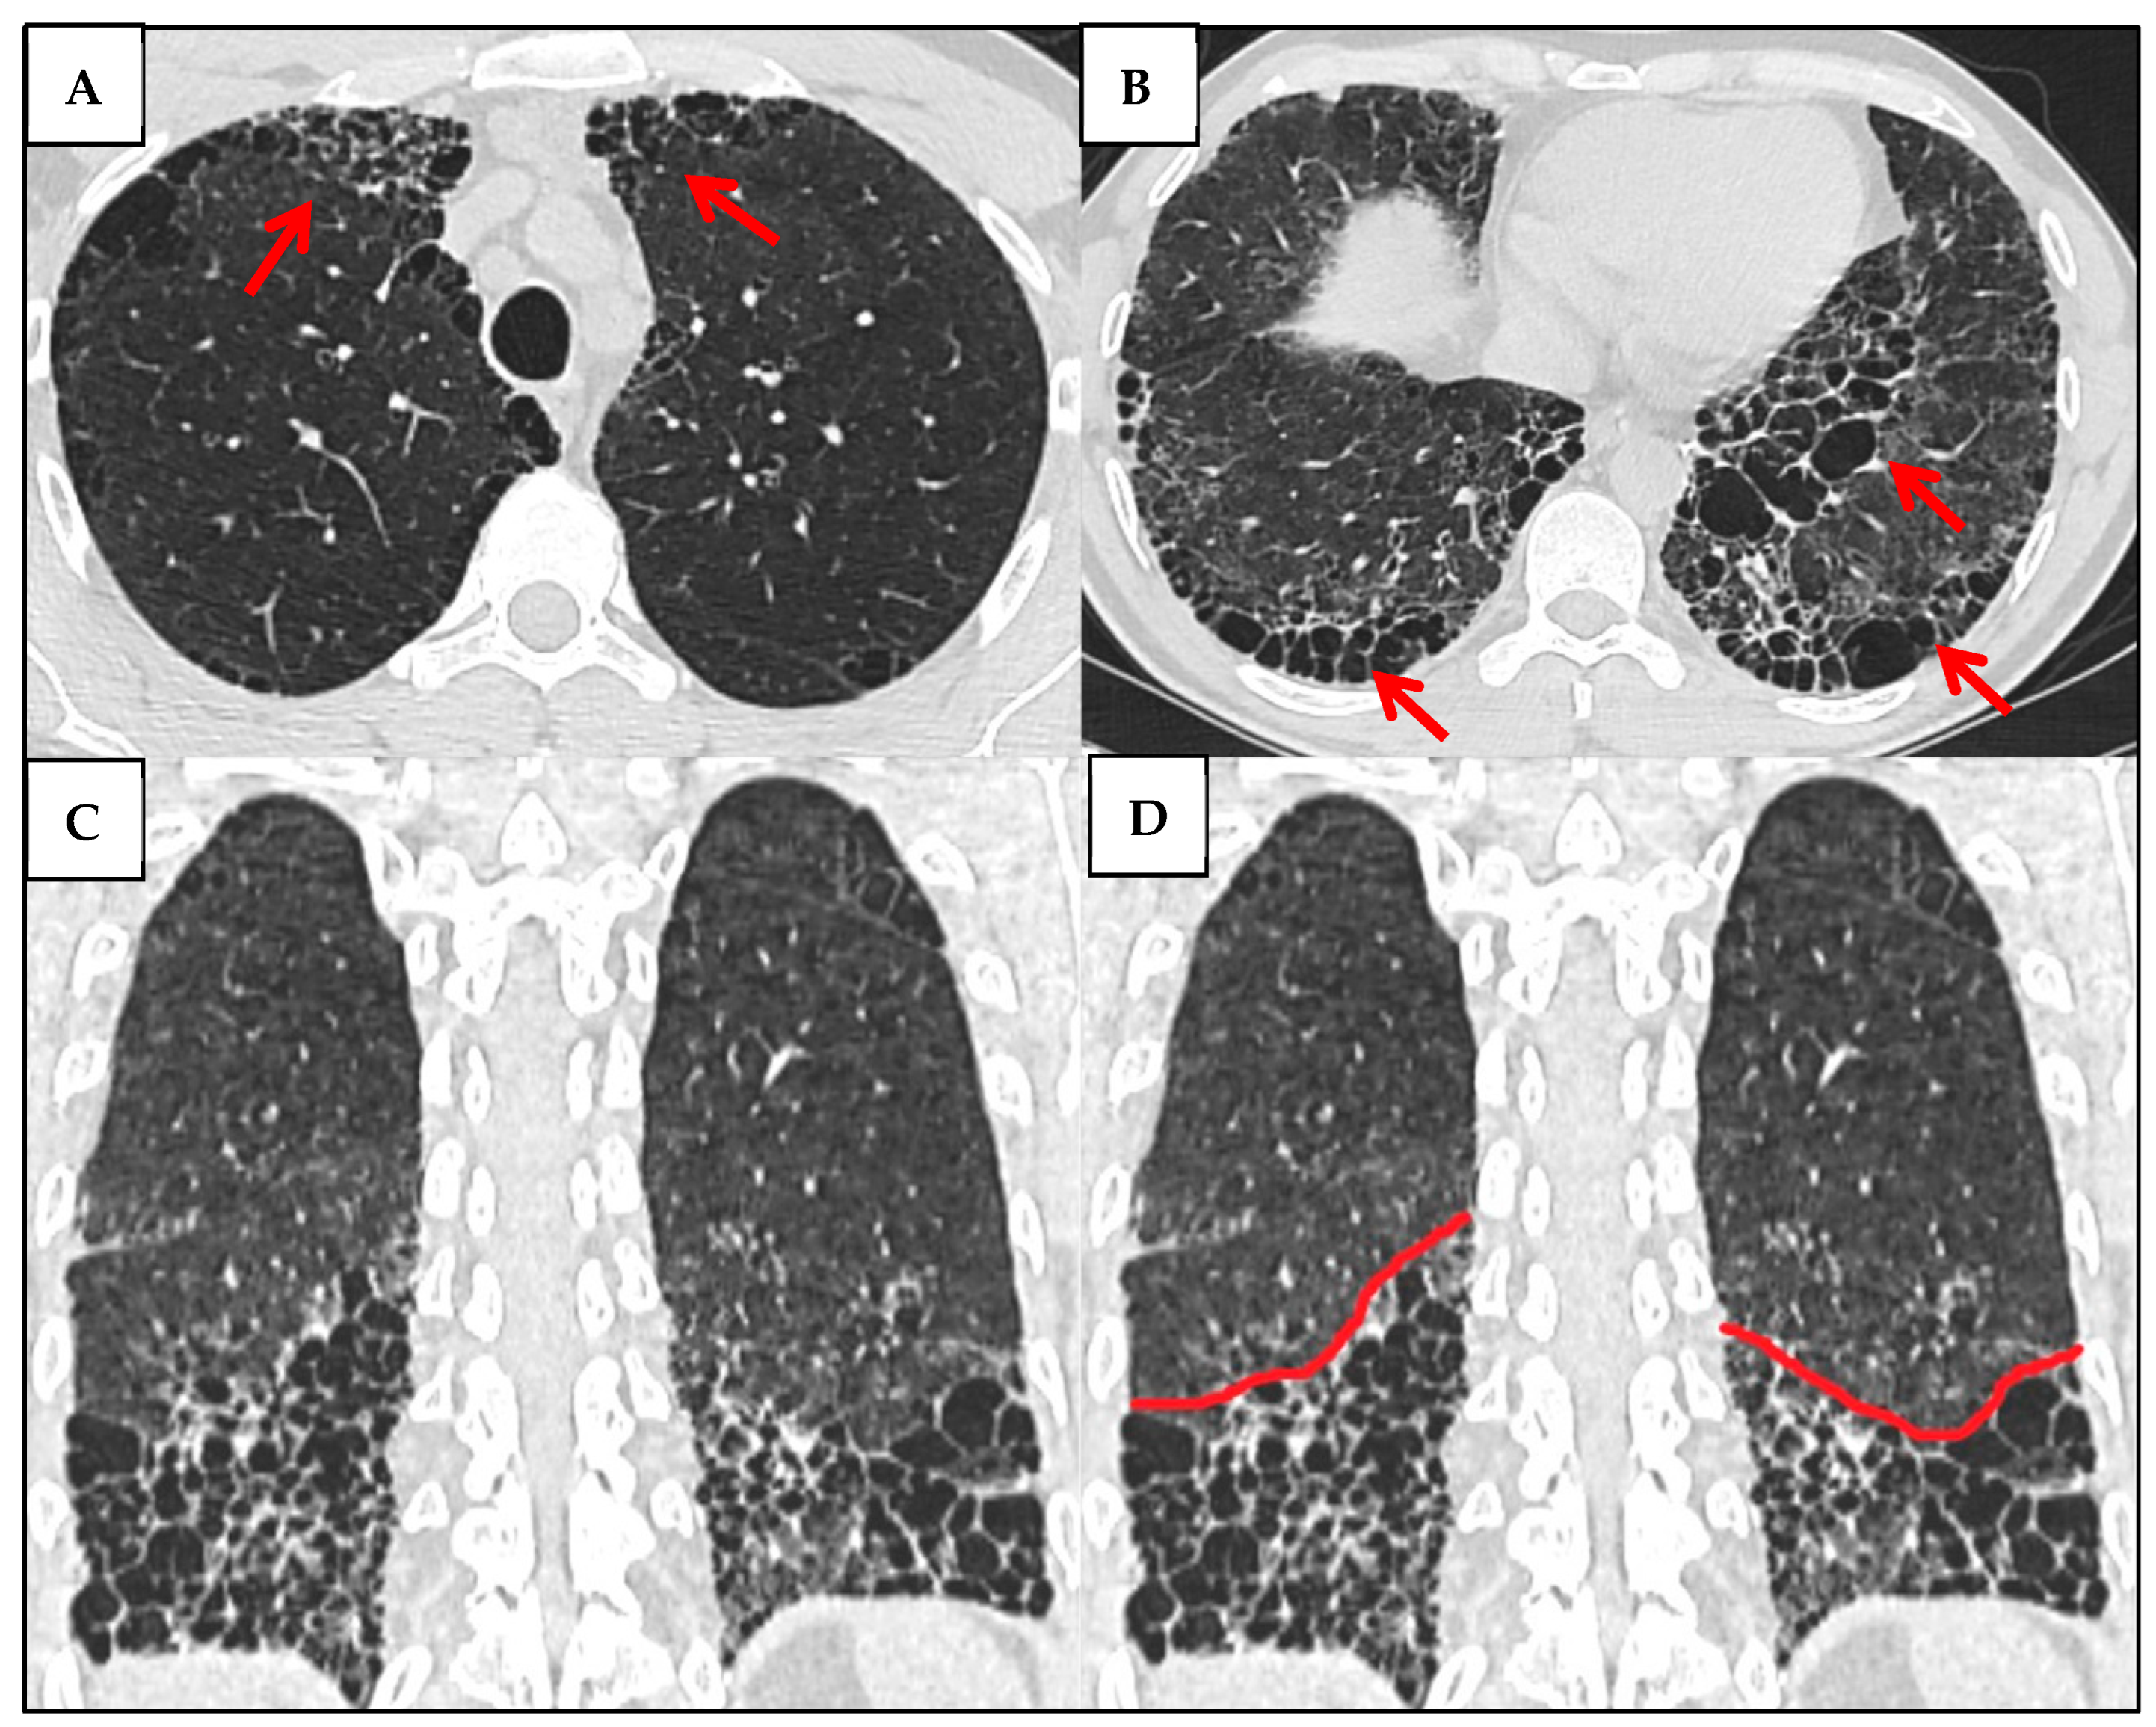

3.3.1. UIP Pattern

| HRCT Patterns | - NSIP (~45–75%): ground-glass opacities, lower lobe predominance - UIP (~20–25%): honeycombing, traction bronchiectasis, worse prognosis - OP (~30%) - Other patterns (~5%)  | [32] |

| HRCT Patterns | - UIP is the most common pattern (~40–60%)—strong negative prognostic marker - NSIP (~15–25%) - OP and mixed types less frequent. (<20%)  | [43] |